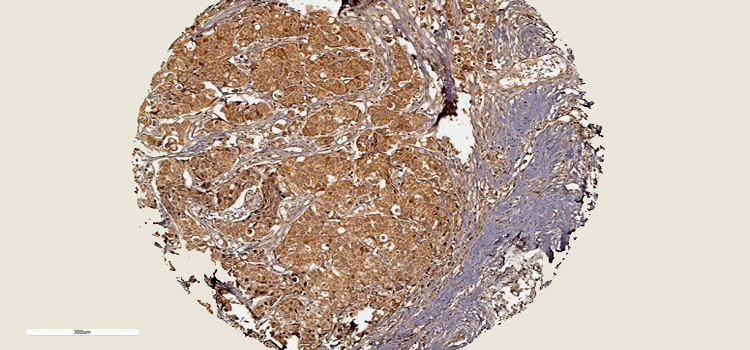

Nuevos patrones en la genética del cáncer apuntan a los genes supresores de tumores como posibles objetivos terapéuticos

29.07.2024

Esta investigación proporciona una hoja de ruta para futuras investigaciones en genética del cáncer. Al explorar las interacciones entre diferentes tipos de cambios genéticos, los científicos pueden obtener una comprensión más profunda de cómo se desarrolla y progresa el cáncer